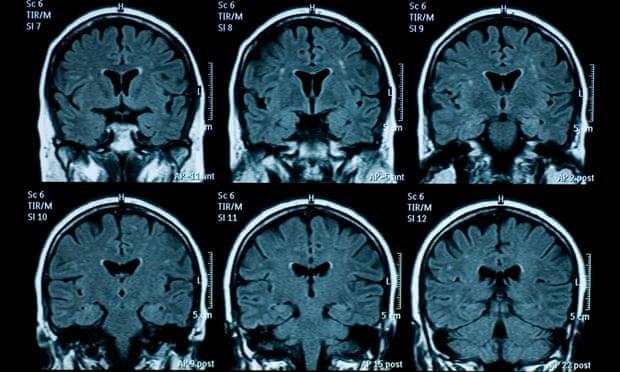

Nghiên cứu mới đây đã phát hiện ra rằng bộ não của những thanh thiếu niên trải qua đại dịch COVID-19 có dấu hiệu lão hóa sớm hơn.